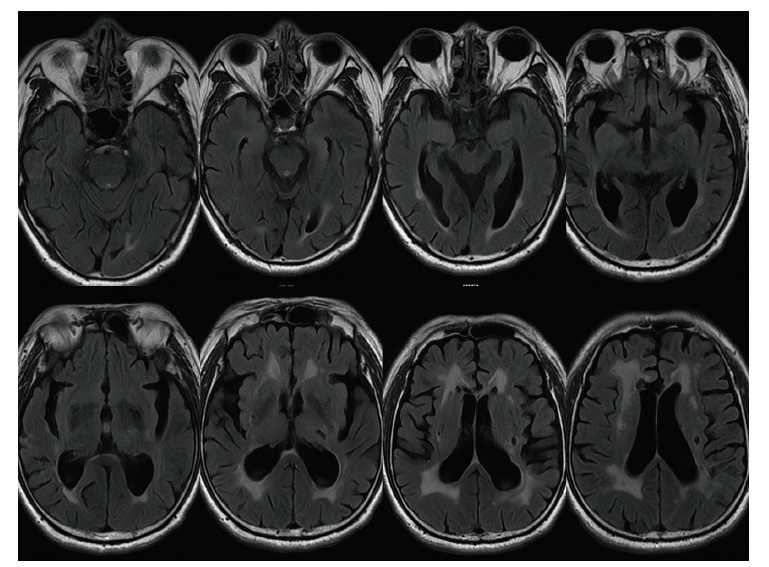

血清及脑脊液LGI1抗体均(+)。脑脊液检查:压力180 mmH2O,氯124.8 mno1/L,葡萄糖3.8 mmol/L,电解质未见异常。颅脑MRI:脑内多发梗死灶及软化灶,部分软化灶周围伴胶质增生(图1)。

图1 一例复发性且MRI阴性的LGI1抗体相关脑炎患者MRI检查

注:T2序列未见异常信号,仅有部分梗死灶及软化灶。

本病的MRI典型表现为单或双侧海马、颞叶的T2及液体衰减反转恢复序列(FLAIR)呈现高信号,部分患者的病灶累及基底节、岛叶及丘脑,亦有部分患者无MRI异常,PET-CT检查则多发现其颞叶内侧或基底节存在异常代谢[14]。本病另一个重要的诊断依据是血清及脑脊液特异性LGI1抗体(+),本例患者MRI未出现异常信号,脑脊液LGI1抗体(+)可作为明确诊断的依据,患者家属暂不同意行PET-CT检查。